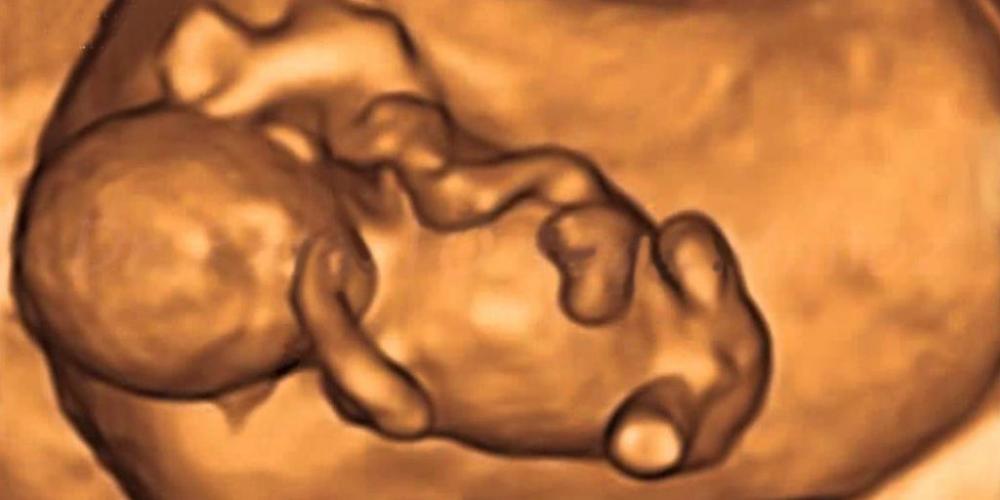

EL ESTADO MATÓ A 98 NIÑOS ARGENTINOS POR DÍA EN 2021